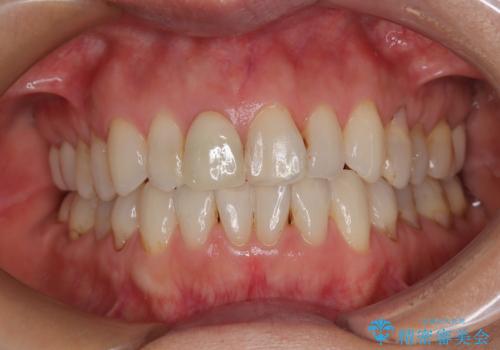

デコボコと銀歯 矯正治療とセラミック治療で綺麗な口元に

- 前歯のデコボコと口を開けたときに見える銀歯を気にして来院された患者様です。

ある程度デコボコが解消されれば大丈夫とのことで、インビザライン・モデレートパッケージを利用して歯列を整えて行くこととしました。

矯正治療後に銀歯をセラミッククラウンなどに置き換えていくと、どうしても後戻りを起こしてしまうため、矯正治療が概ね終了した時点で銀歯を全てセラミックとし、最後に仕上げでインビザラインにを用いて細かいデコボコを改善していくこととしました。

とても明るい口元となり、人目を気にせず、大きく口を開けて笑えるようになりました。